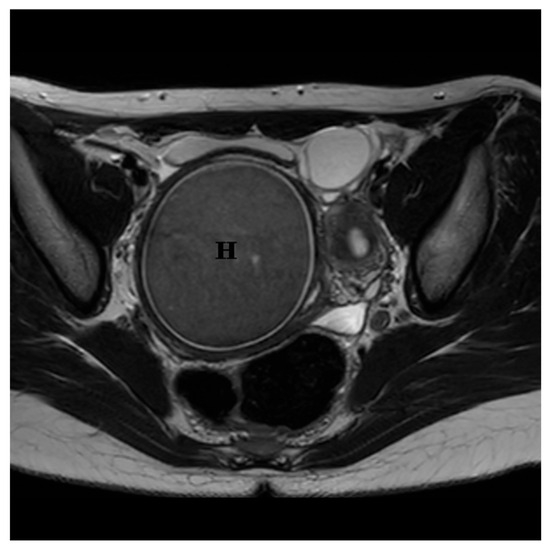

Mayer–Rokitansky–Kuster–Hauser Syndrome: From Radiological Diagnosis to Further Challenges—Review and Update

by Calin Schiau, Csaba Csutak, Anca Ileana Ciurea, Roxana Pintican, Ioana-Teofana Dulgheriu and Simona Manole

Diagnostics 2026, 16(1), 138; https://doi.org/10.3390/diagnostics16010138 - 1 Jan 2026

Mayer–Rokitansky–Küster–Hauser (MRKH) syndrome encompasses a range of Müllerian duct anomalies characterized by congenital absence of the uterus and the upper two-thirds of the vagina in young women who otherwise exhibit normal endocrine function and a 46,XX karyotype. MRKH syndrome can occur in an [...] Read more.

Mayer–Rokitansky–Küster–Hauser (MRKH) syndrome encompasses a range of Müllerian duct anomalies characterized by congenital absence of the uterus and the upper two-thirds of the vagina in young women who otherwise exhibit normal endocrine function and a 46,XX karyotype. MRKH syndrome can occur in an isolated form (type I) or in association with other congenital anomalies (type II or MURCS association), which may include renal, vertebral, auditory, and cardiac defects. It represents one of the most frequent causes of primary amenorrhea, affecting approximately 1 in every 4000–5000 women. MRKH syndrome often remains undiagnosed until a patient presents with primary amenorrhea, despite normal development of secondary sexual characteristics. Both genetic and non-genetic factors have been proposed as contributing to abnormal embryonic development, although the exact etiopathogenesis remains unclear. Imaging plays a key role in the evaluation of genital tract anomalies, allowing non-invasive and comprehensive assessment. Alongside physical examination and pelvic ultrasound, pelvic MRI is essential for identifying the presence of rudimentary uterine tissue. MRKH syndrome can have profound and lasting psychological impacts, making it essential for patients and their families to receive counseling both before and throughout treatment. A range of therapeutic options—both surgical and non-surgical—have been proposed for managing MRKH syndrome. Vaginal dilation remains the first-line treatment, as it offers high success rates with minimal risk of complications. Vaginoplasty is considered a second-line option for patients who do not respond to dilation therapy. Additionally, uterine transplantation and gestational surrogacy provide opportunities for women with MRKH syndrome to achieve biological motherhood. This review provides an updated overview of Mayer–Rokitansky–Küster–Hauser (MRKH) syndrome, encompassing its etiological, clinical, diagnostic, psychological, therapeutic, and reproductive aspects. We also present a case involving a 19-year-old woman with MRKH syndrome who presented with primary amenorrhea, highlighting the crucial role and advantages of MRI in diagnosis, differential assessment, and treatment planning. Full article